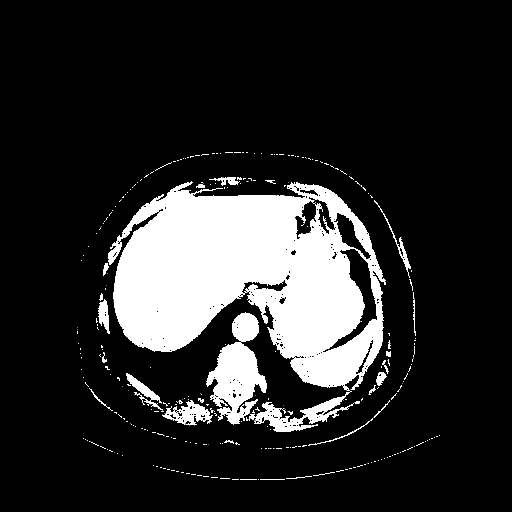

Original NATIVE CT scan (input)

Full window (WL 1023.5, WW 4095 β†’ Low βˆ’1024, High +3071)

Actual HU range: [-1024.0, 3071.0]